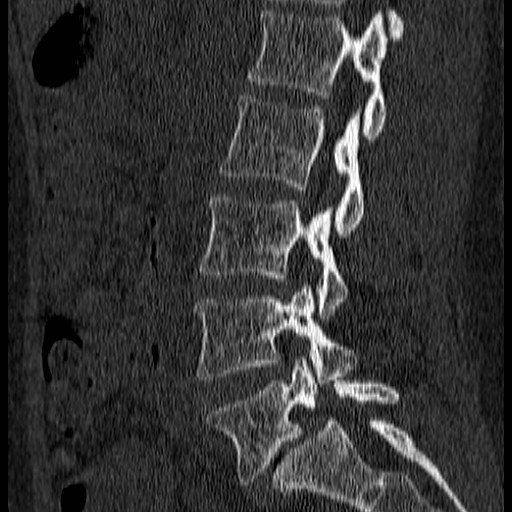

CT scans:

“CAT” scans are a high-tech way at looking inside you. They use radiation and require the benefits to be weighed against the risk. They provide me with information that other tests may not. This test conveys precise anatomical detail and eliminates sinister pathologies.

EXAMPLE OF FUSION SURGERY:

The images show how I treat a stress fracture of the lowest bone in the spine.

On this CT. The bones to the right of the image lie on top of each like roof tiles. The roof tile is disrupted in the lowest image because of a fracture (i.e a broken bone)

The disc space is seen to be distorted and the lower bone has changed to a white colour which can be a sign that this is causing pain.